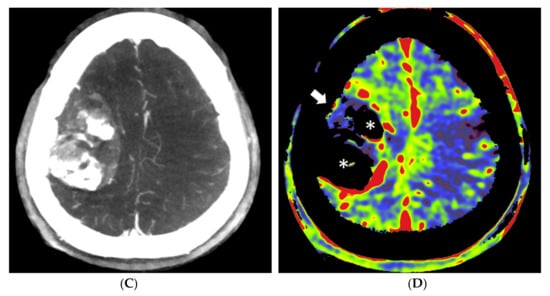

In patient no. 3, with a transitional meningioma located at the left sphenoid ridge, a predominant pial vascular supply was present. No embolization was done because it was considered not helpful for the resection (Figure 3).

Figure 3.

Patient no. 3 presented with a very large sphenoid ridge meningioma on the left side. (A) Axial 3 mm reformation based on fill run images shows the large tumor with encasement of the distal internal carotid artery (arrow) and the middle cerebral artery on the left. (B) Coronal reformation of whole brain PBV perfusion imaging compared to (C) coronal reformation of selective PBV perfusion by injection of the left external carotid artery shows predominant pial blood supply and only limited dural supply to the tumor. In this case, pre-operative embolization was not pursued because it was considered not helpful for reducing the surgery risk in comparison to the risk of the embolization procedure.

The operation time varied between 3 h and 40 min (patient no. 5) to 14 h (patient no. 3) of surgery. The longest operation time correlated with the patient with the predominant pial arterial supply (patient no. 3, Figure 3), in which an external to internal bypass (from superficial temporal artery to middle cerebral artery) was constructed. Negligible blood loss (<50 mL) was present in patients no. 2, 4 and 5. In patients no. 1 and 3, a blood loss of 500 mL and 300 mL was observed, respectively. The post-operative course was uneventful for all patients.